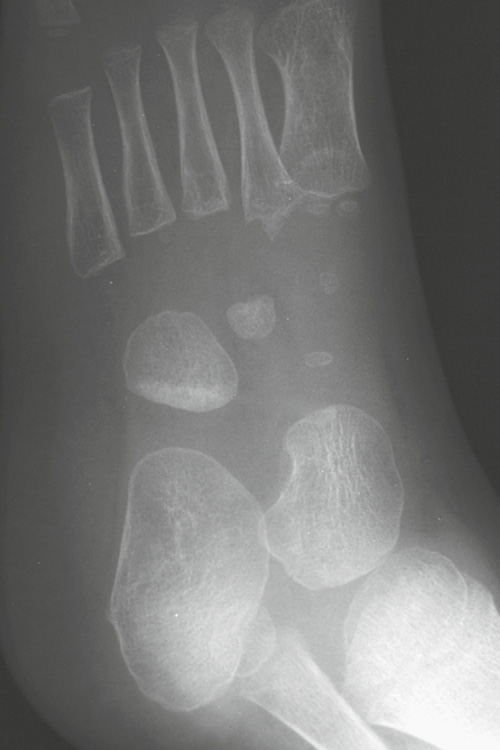

Common sites for Toddler’s fracture

• tibial midshaft

• proximal anterior tibia

• calcaneus

• cuboid